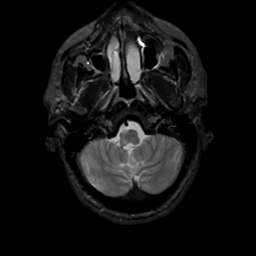

MR Study #4, March 3, 1991 -- Slice #7